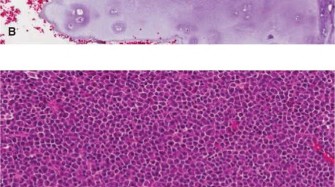

For Atypical Cartilaginous Tumors, a cortical window is created over the lesion. The window should be oval or rectangular with rounded corners to minimize stress risers. The window must be large enough to allow complete visualization of the tumor cavity.

Intralesional curettage is performed systematically. Hand curettes are used to remove the gross macroscopic tumor, which typically appears as glistening, bluish-white, avascular lobules of cartilage. Following gross removal, a high-speed mechanical burr is utilized to extend the curettage 1 to 2 millimeters into normal-appearing cancellous and cortical bone. This mechanical adjuvant is critical for removing microscopic tumor extensions within the trabecular bone.

Image

Chemical or physical adjuvants are subsequently applied to the cavity to induce necrosis of any remaining microscopic disease. Phenol (followed by alcohol neutralization), hydrogen peroxide, or liquid nitrogen (cryotherapy) are commonly employed. When using cryotherapy, careful protection of the surrounding soft tissues and neurovascular structures is imperative to prevent iatrogenic thermal injury. Multiple freeze-thaw cycles provide the maximum tumoricidal effect.